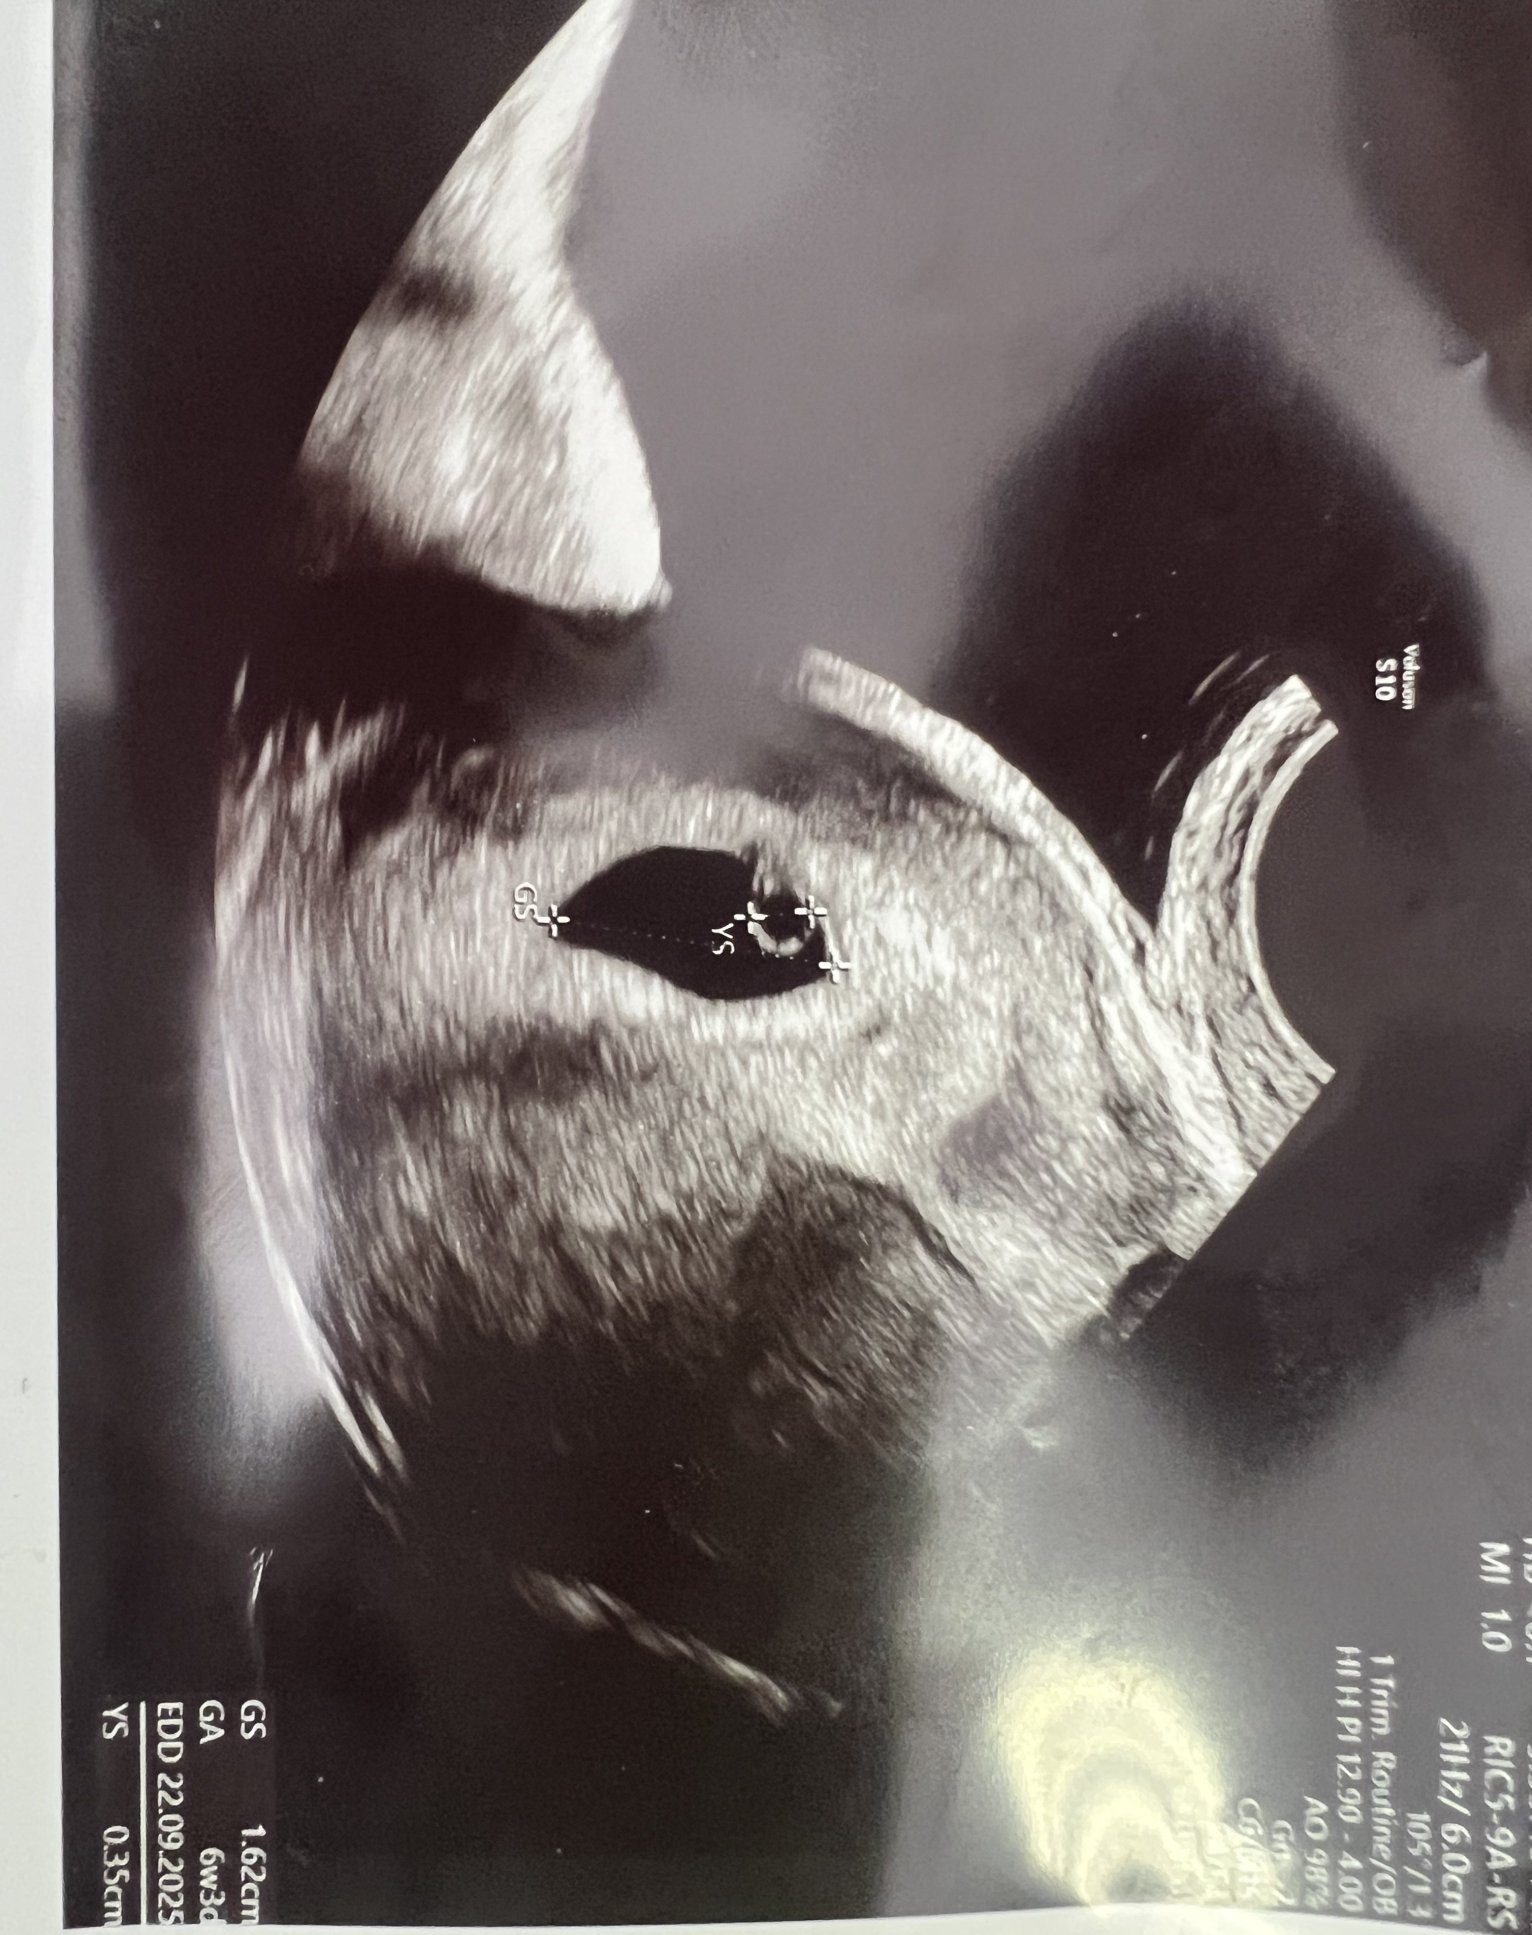

Здравейте момичета, днес мина и моят преглед, видяха се ембрион и сърдечна дейност, и въпреки това, притеснението продължава да го има. При вас така ли е ? 🥹

Момичета ходих вчера на преглед и малко се притесних, видя се жълтъчно мехурче но нямаше ембрион в 6 + 3 г.с. съм ,търси и пулс, но нямаше. Каза, че към момента нищо освен мехурчето и сака не се вижда.